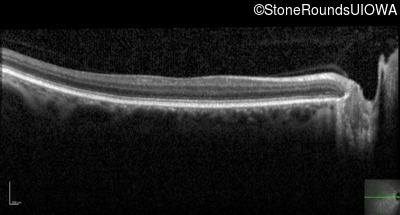

Optical Coherence Tomography - Right - 20/100 -2 sc

Exemplar / OCT Stack

OCT Stack